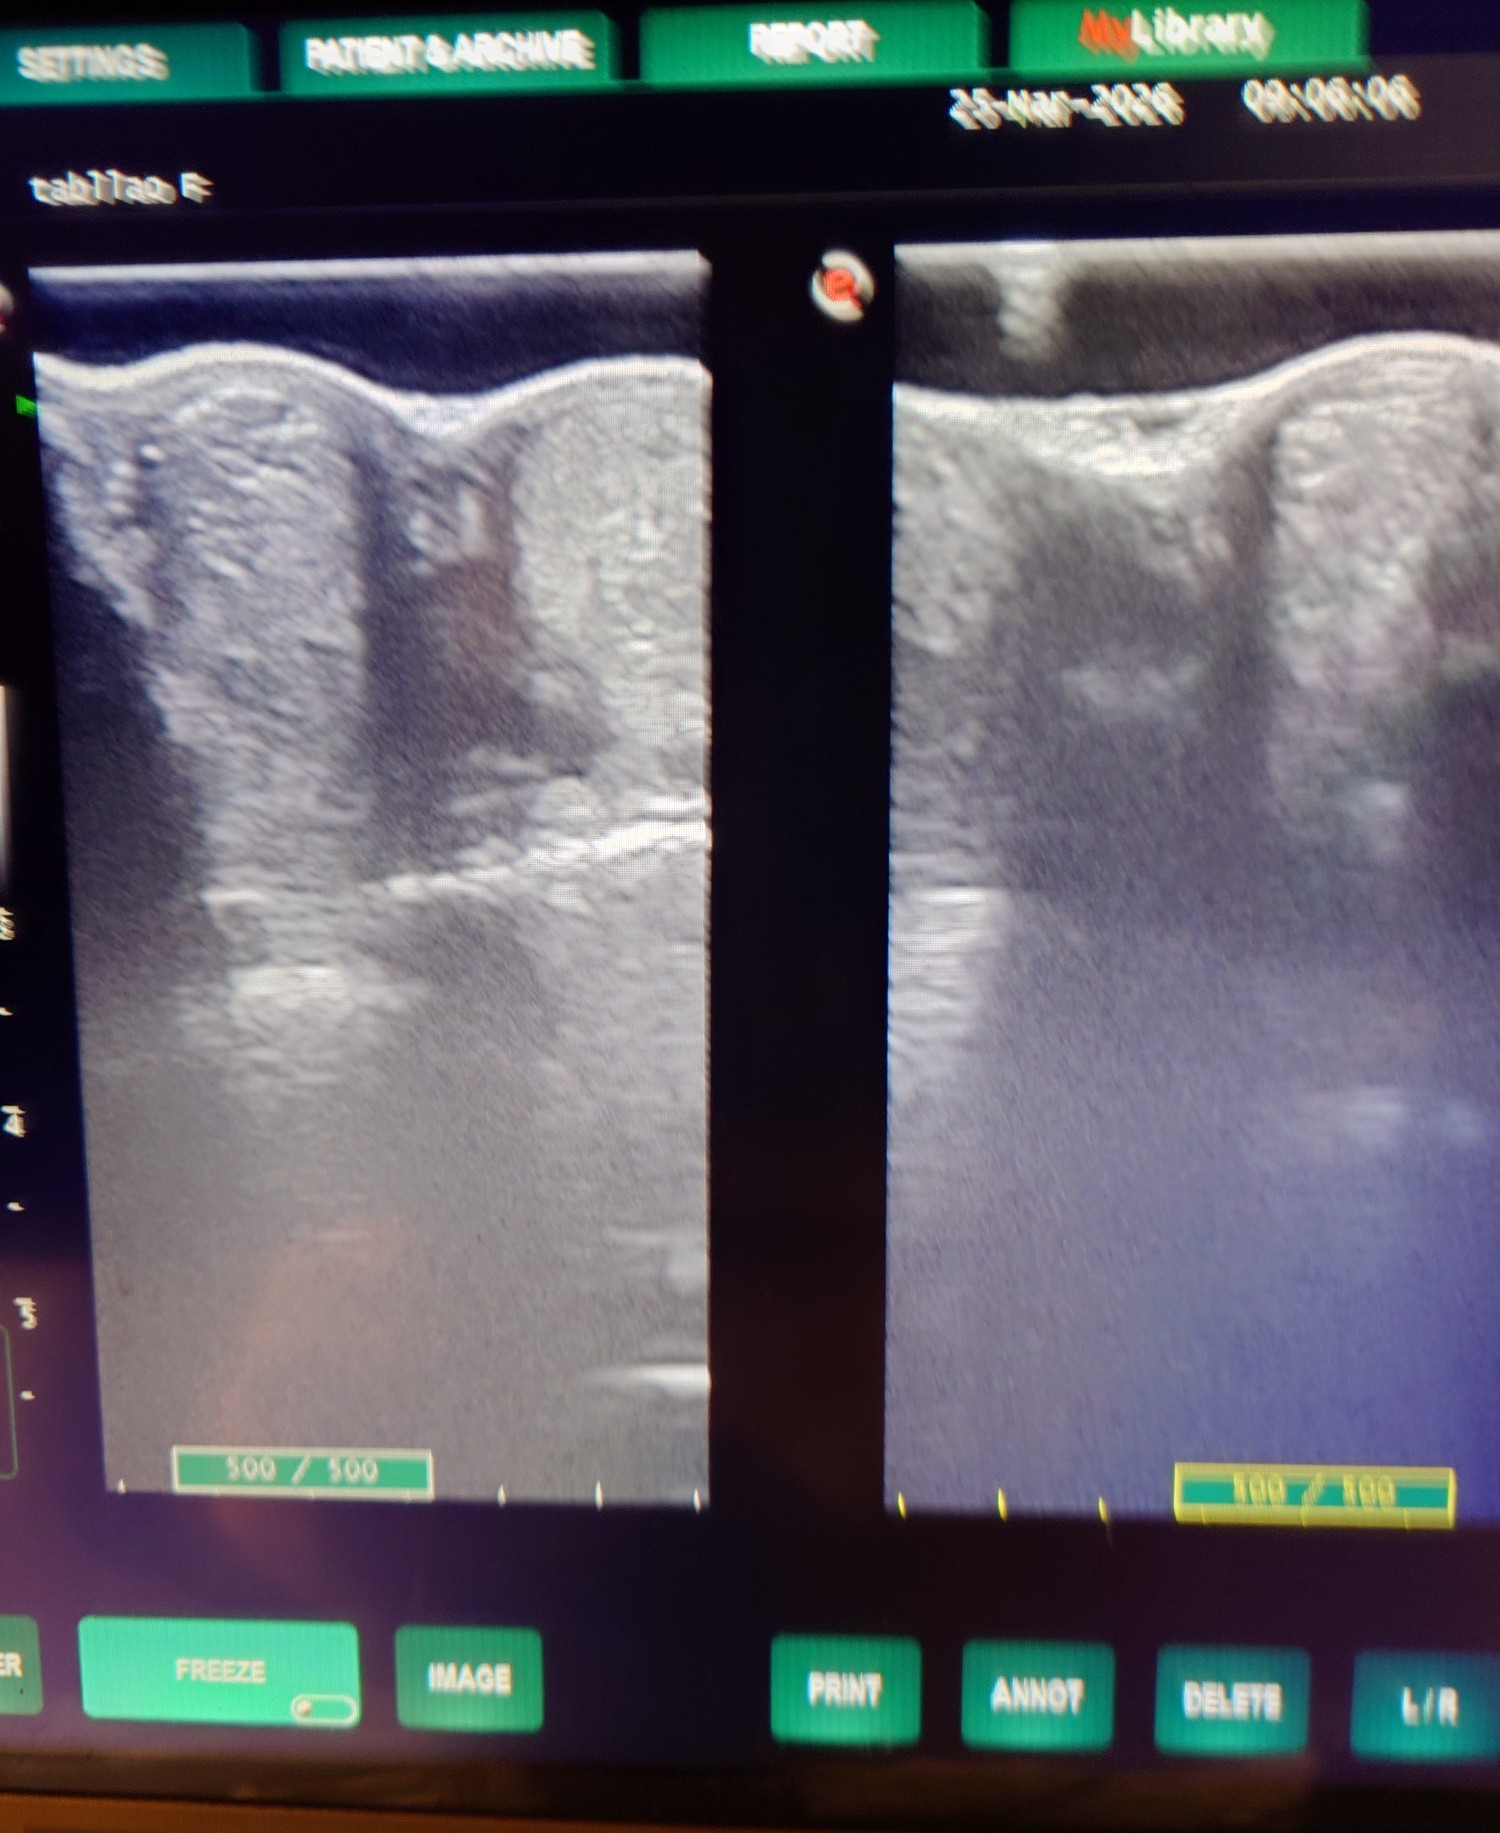

2012年にケンタッキーダービーを制した父アイルハヴアナザー産駒はアナザートゥルース(セン12歳)、オメガレインボー(牡10歳)他、タフなダート馬が多い。本馬は2歳時の6月に大井競馬場で新馬勝ちし、ハイセイコー記念6着後、3連勝で雲取賞へ臨み3着。羽田盃、東京ダービー後、休養して秋はA2B1クラスで出走しましたが惨敗が続いたため4歳時の2月28日に去勢。その後も結果を出せませんでしたが、5歳の8月にライアンクアトロ騎手が跨って快勝。そこからコンスタントに出走してA2(JRA交流2勝)クラスの特別戦で4勝を挙げました。8歳になった今年の3月の川崎戦で8着後、左前脚の球節が腫れてしまい、レントゲン検査で骨膜を発症していることが判明しました。剥がれかかっており、獣医師から全治3~4カ月と診断されたため現役を断念、引退することになりました。